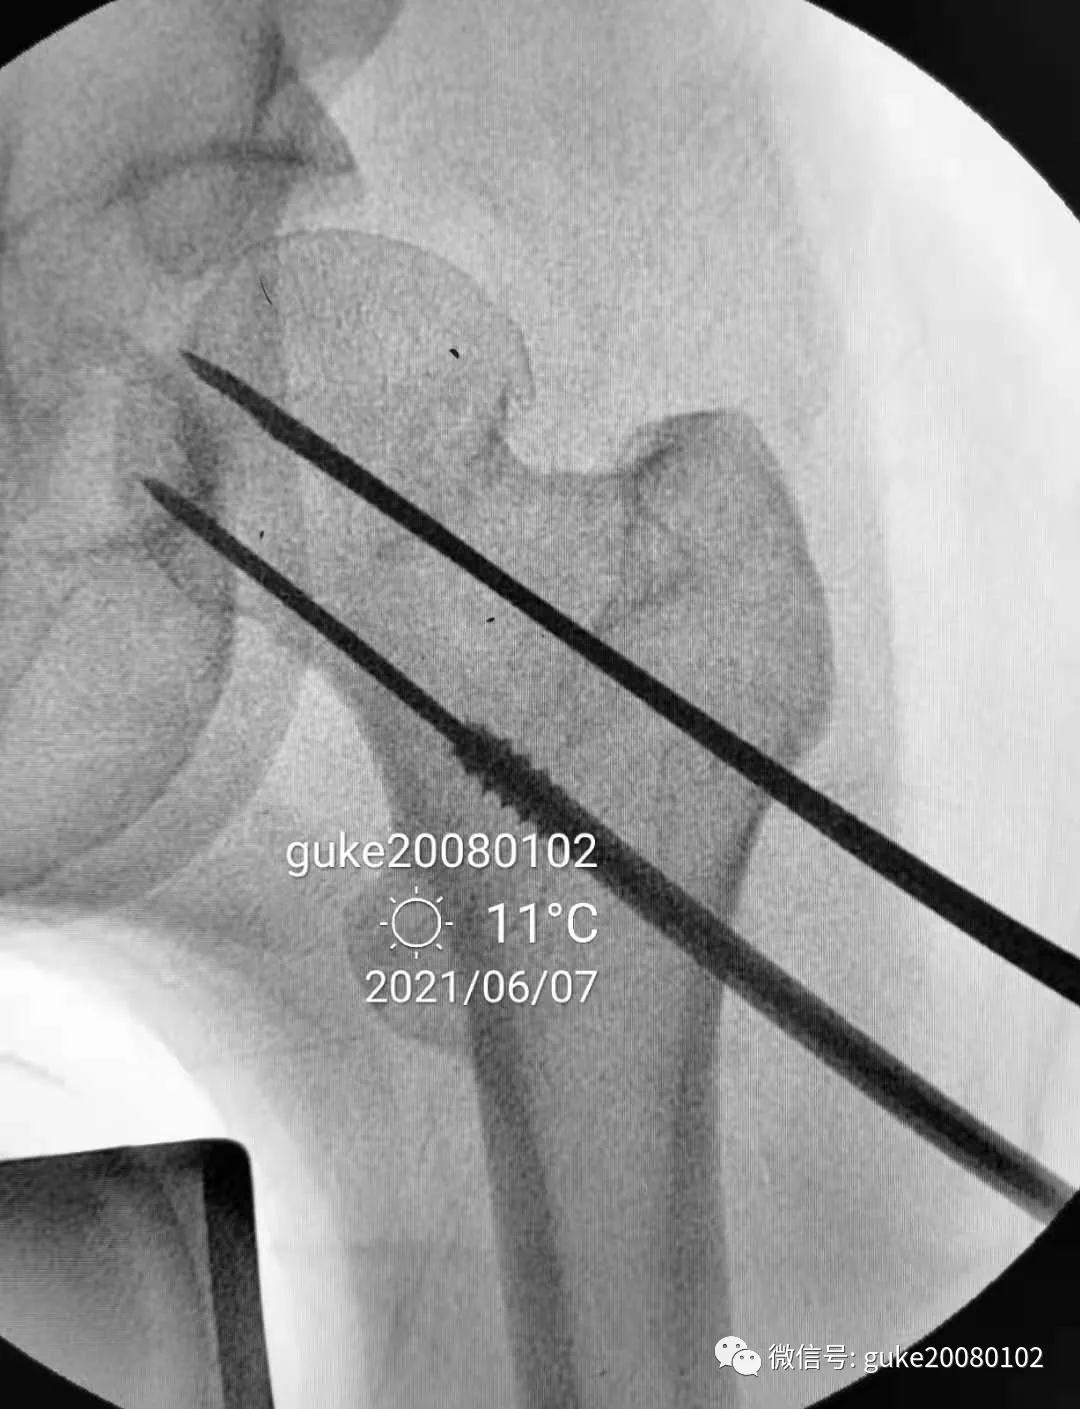

患者置于牵引床上,固定骨盆,尝试Ledbetter法复位,透视见复位不佳。骨折断端崁插,股骨头外翻。

- 在大转子顶点近端5厘米处,经皮向股骨头上方插入直径2.0mm克氏针两枚,敲击克氏针至骨质,撬拨头颈骨折块复位。

- 撬拨力量偏小,骨折复位不足。再插入一枚2.5mm克氏针,接力撬拨,骨折复位。